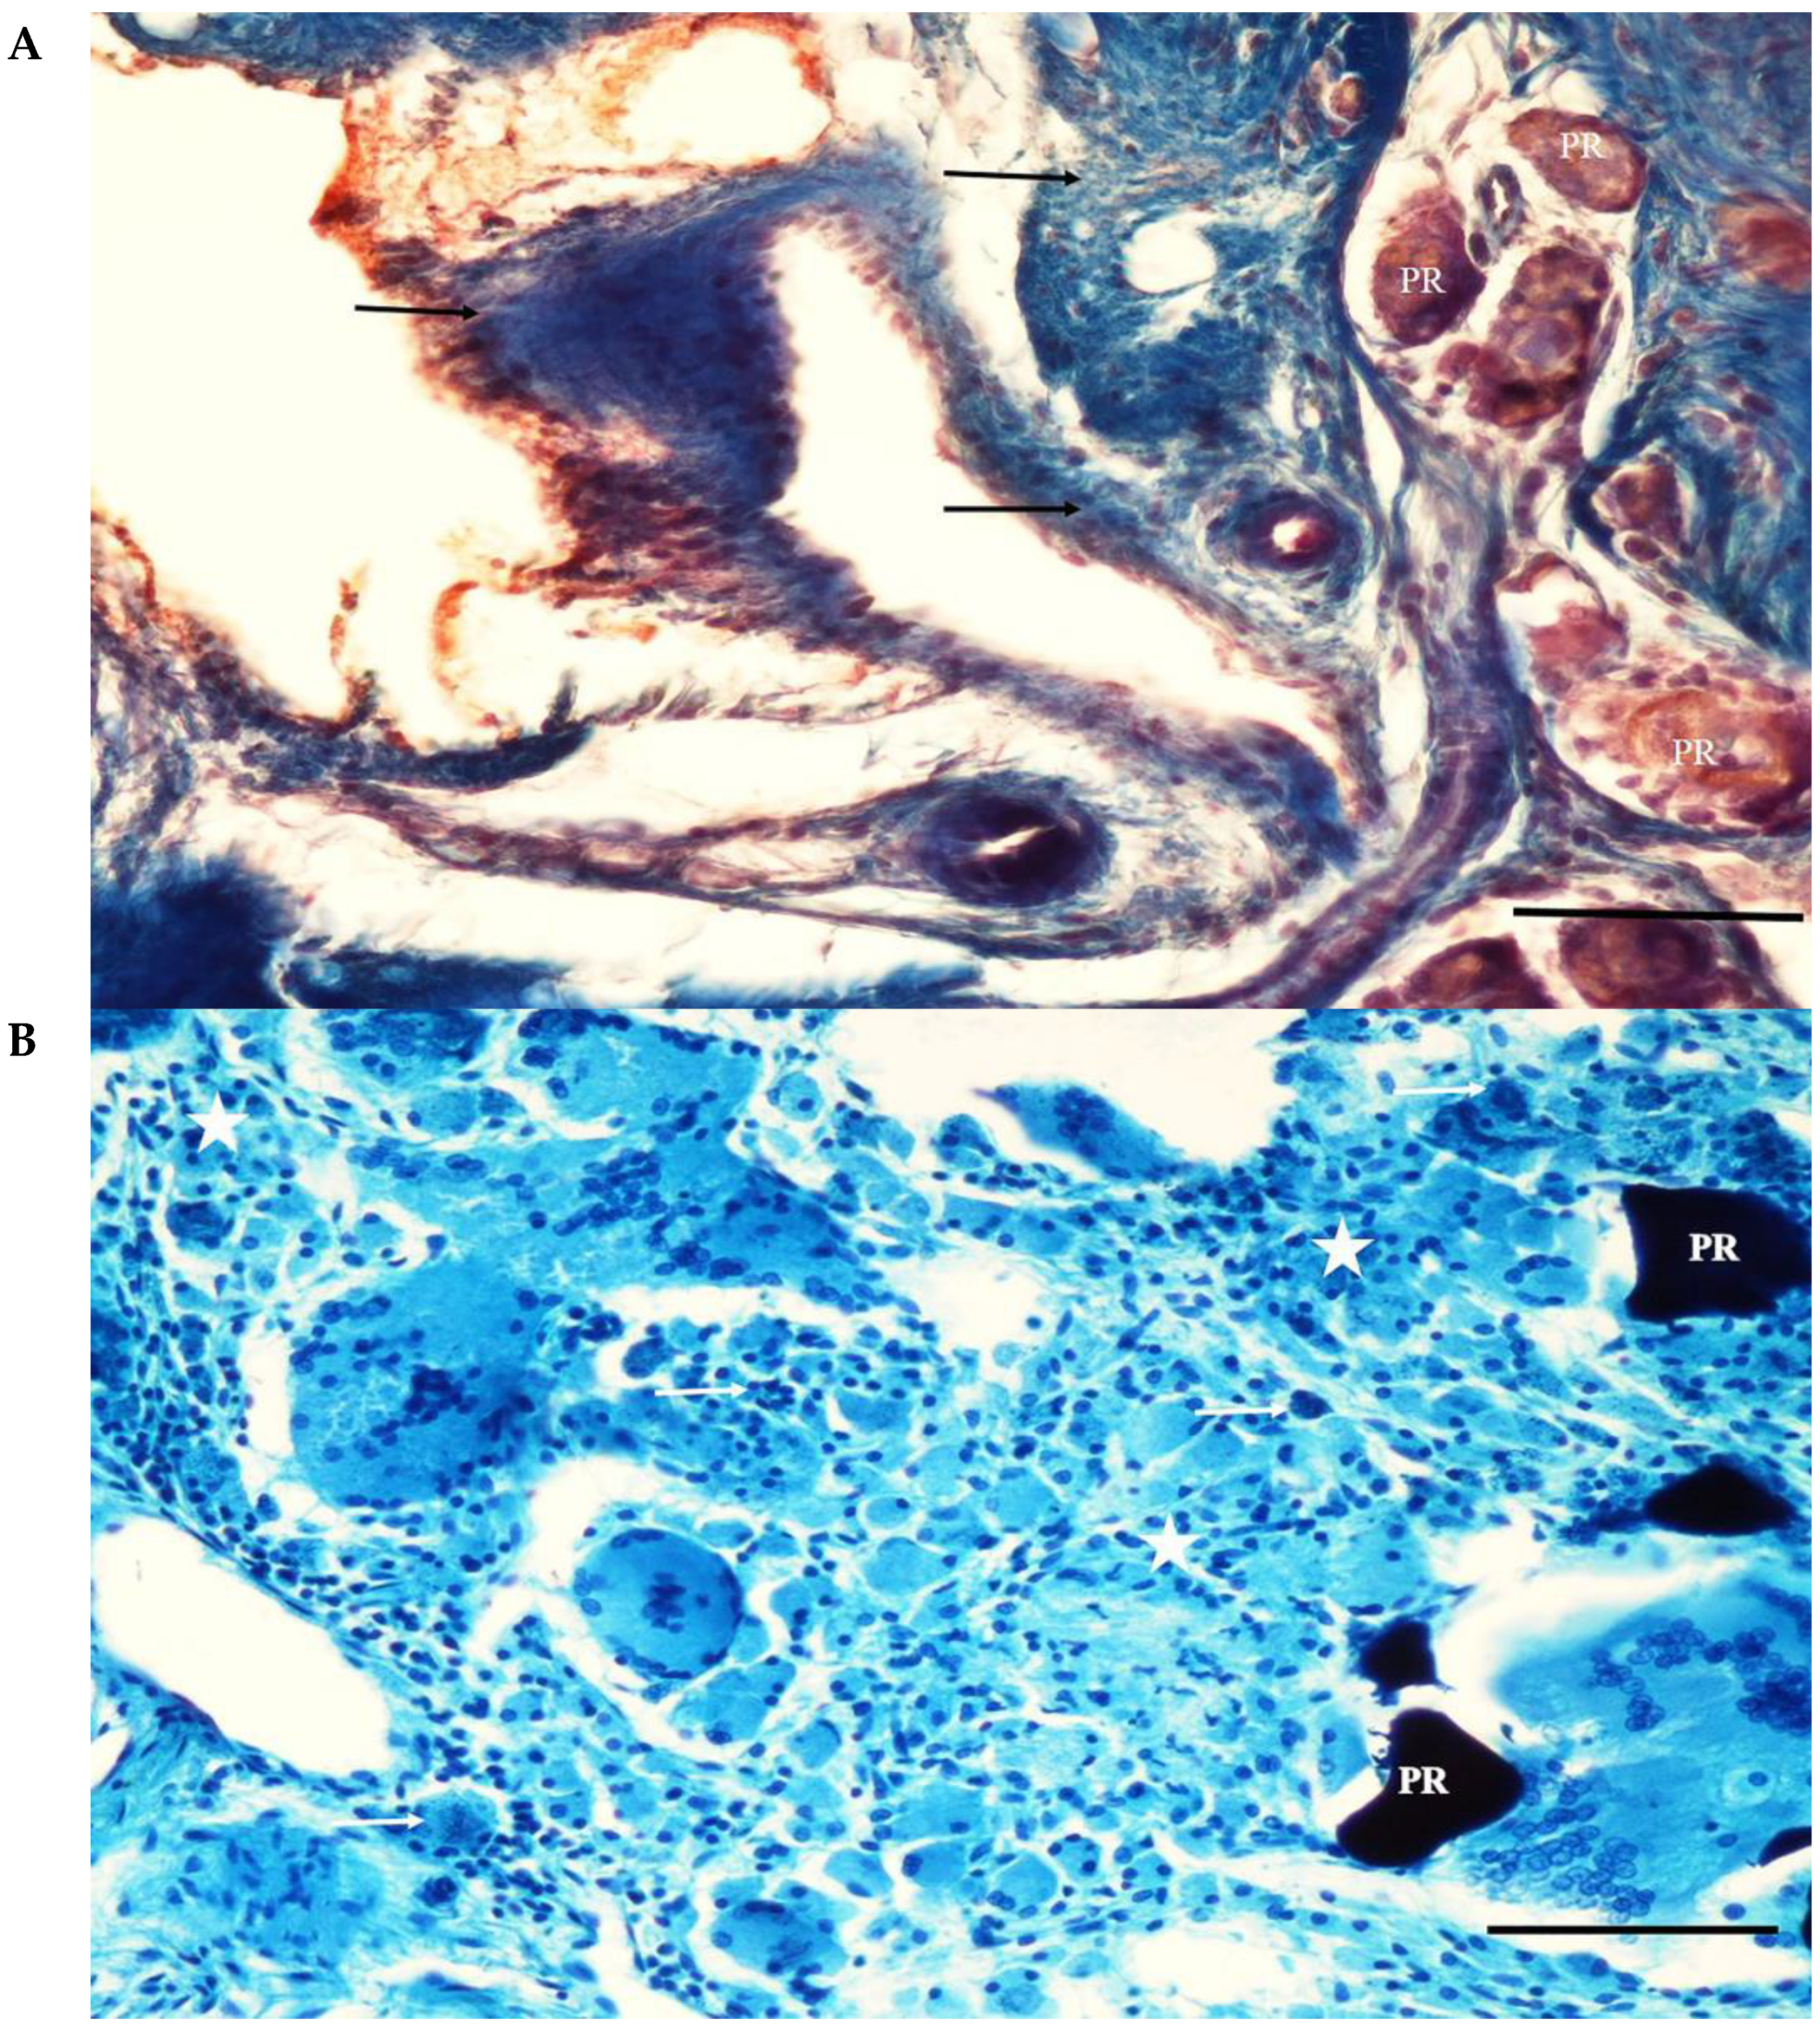

The screw bodies in the cortical region of the MP+ group were covered with tissue similar to that of the PC group. The eggshell particles were highly resorbed in the adjacent socket. Thin bone trabeculae lined with osteoblastic cells surrounded some of the particles. The interarticular region was filled with blood vessels and connective tissue rich in mononuclear cells. Intense mononuclear cell infiltration and a few multinucleated foreign-body giant cells were observed in some areas. Fibrous capsule formation surrounding the particles was not observed (Figure 8).

Figure 8.

(A) A section from the adjacent defect of the MP+ group. The eggshell particles (PR) are highly resorbed. Thin bone trabeculae (T) lined with osteoblastic cells (arrows) surround some of the particles. Pappenheim’s panoptic stain Magnification bar: 100 µm. (B) A section from the adjacent defect site of the MP+ group. Thin bone trabeculae (T) surround a highly resorbed eggshell particle (PR). Adipose cells (asterisks) and connective tissue rich in mononuclear cells (arrow) fill between the particle remnants. Intense mononuclear cell infiltration is evident. Fibrous capsule formation surrounding the particles is not seen. Haematoxylene-eosin staining. Magnification bar: 100 µm.